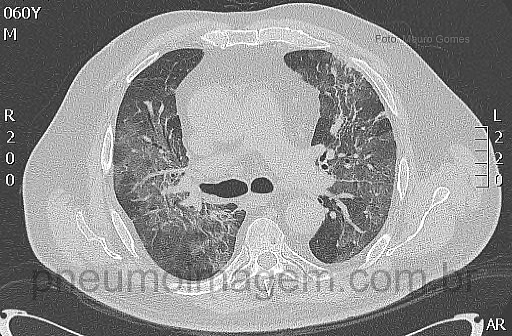

Paciente do sexo masculino, 60 anos, com histórico de quadro gripal há 4 dias associado à febre. Há um dia com dispneia, tosse produtiva, deu entrada no Serviço de Emergência em insuficiência respiratória e importante dessaturação. Nega antecedentes pulmonares ou tabagismo, nega epidemiologia para AIDS. Portador de Púrpura Trombocitopênica Idiopática (PTI), realizou esplenectomia há um mês.

Eutrófico, consciente, contactuando, taquidispneico, cianose de extremidades, desidratado, corado. Hipotenso (90 x 50mmHg), taquipneico (30/min), taquicárdico (120R), afebril (37,2C), IMC: 33. Estertores crepitantes difusos em ambos os pulmões. Faça sua hipótese diagnóstica e deixe seus comentários abaixo.

Male patient, 60 years, flu-like symptoms for 4 days associated with fever. Dyspnea and productive cough for one day, was admitted to the emergency department in respiratory insufficiency and significant desaturation. He denies pulmonary diseases, smoking and AIDS epidemiology. Idiopathic Thrombocytopenic Purpura antecedent (ITP), splenectomy performed a month ago.

Eutrophic, conscious, tachydyspneic, cyanosis, dehydrated. Hypotensive (90 x 50 mm Hg), tachypnea (30/min), tachycardia (120R), afebrile (37.2 C), BMI: 33. Diffuse crackles in both lungs. Leave your comments below.